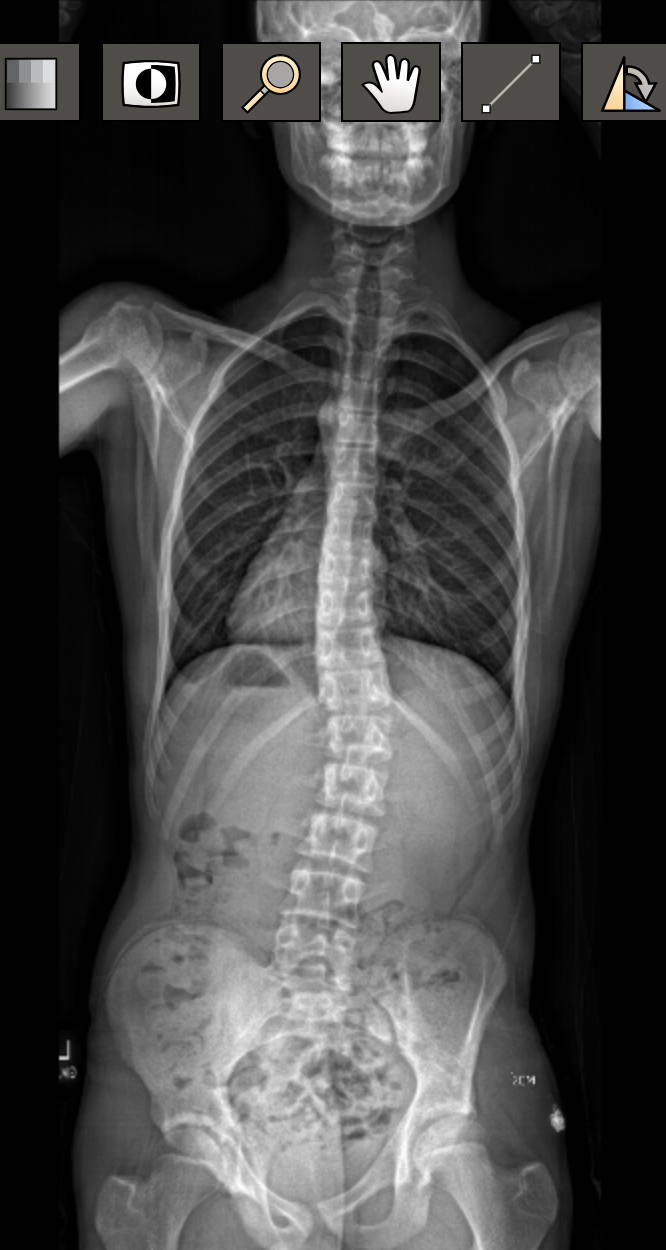

What is Scoliosis?

Any curvature in the spine that measures larger than 10 degrees, that causes the spine to deform in three dimensions. This could be triggered in adolescence (or earlier), as a result of an injury, or from a degenerative condition that presents as we age